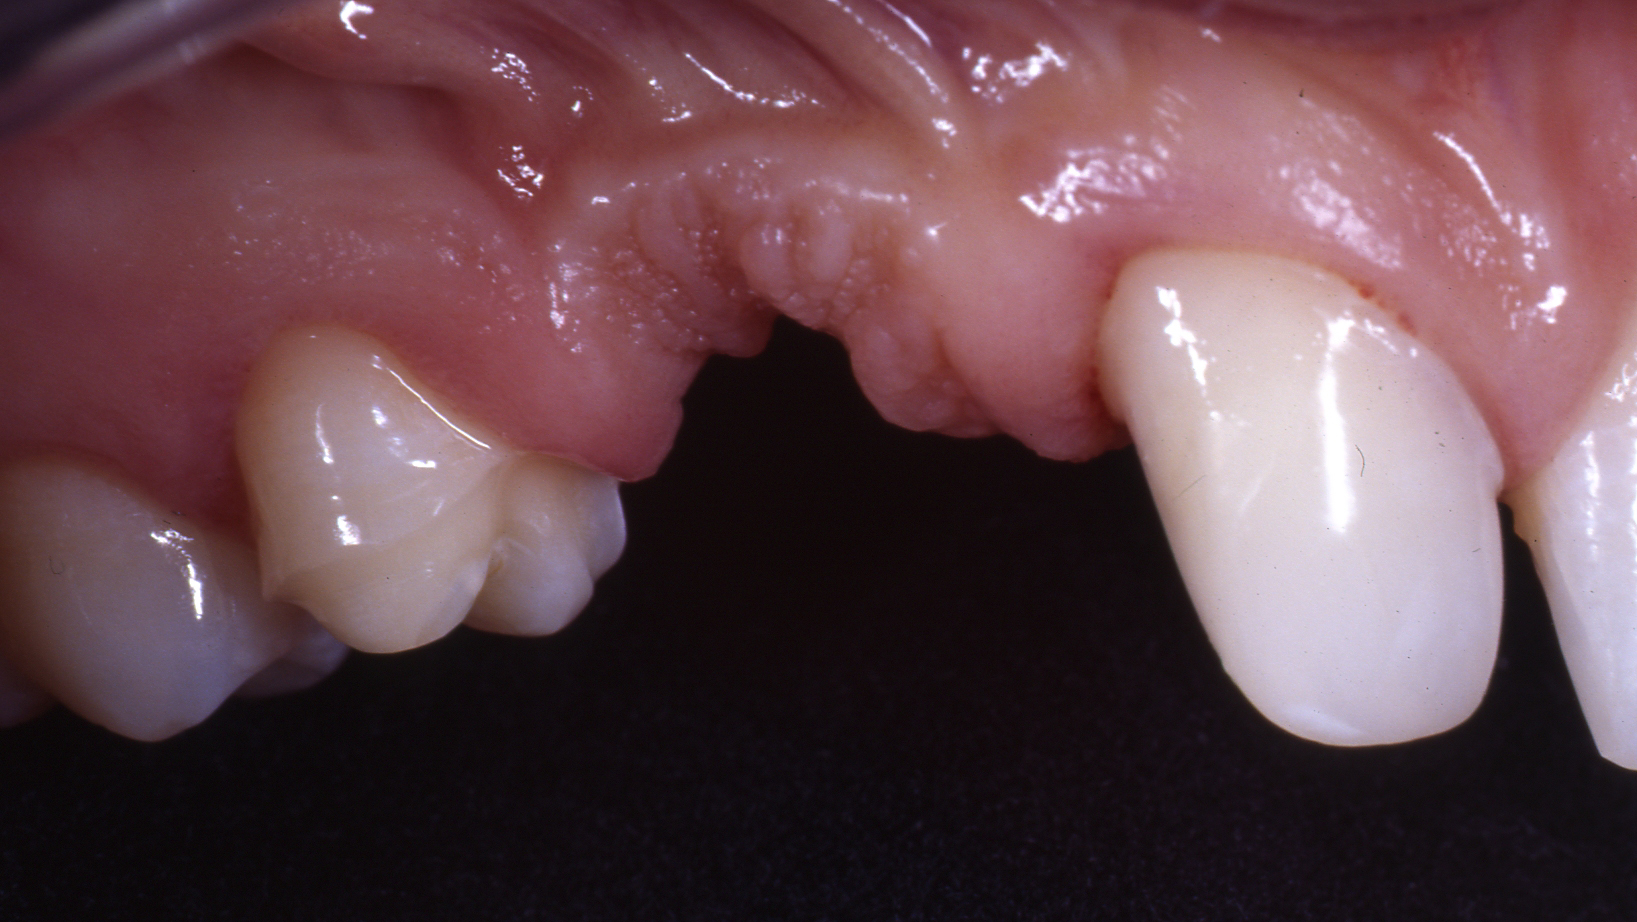

Vollkeramische Teilungsbrücke zum Ersatz der fehlenden Zähne und minimalinvasiver Verankerung.